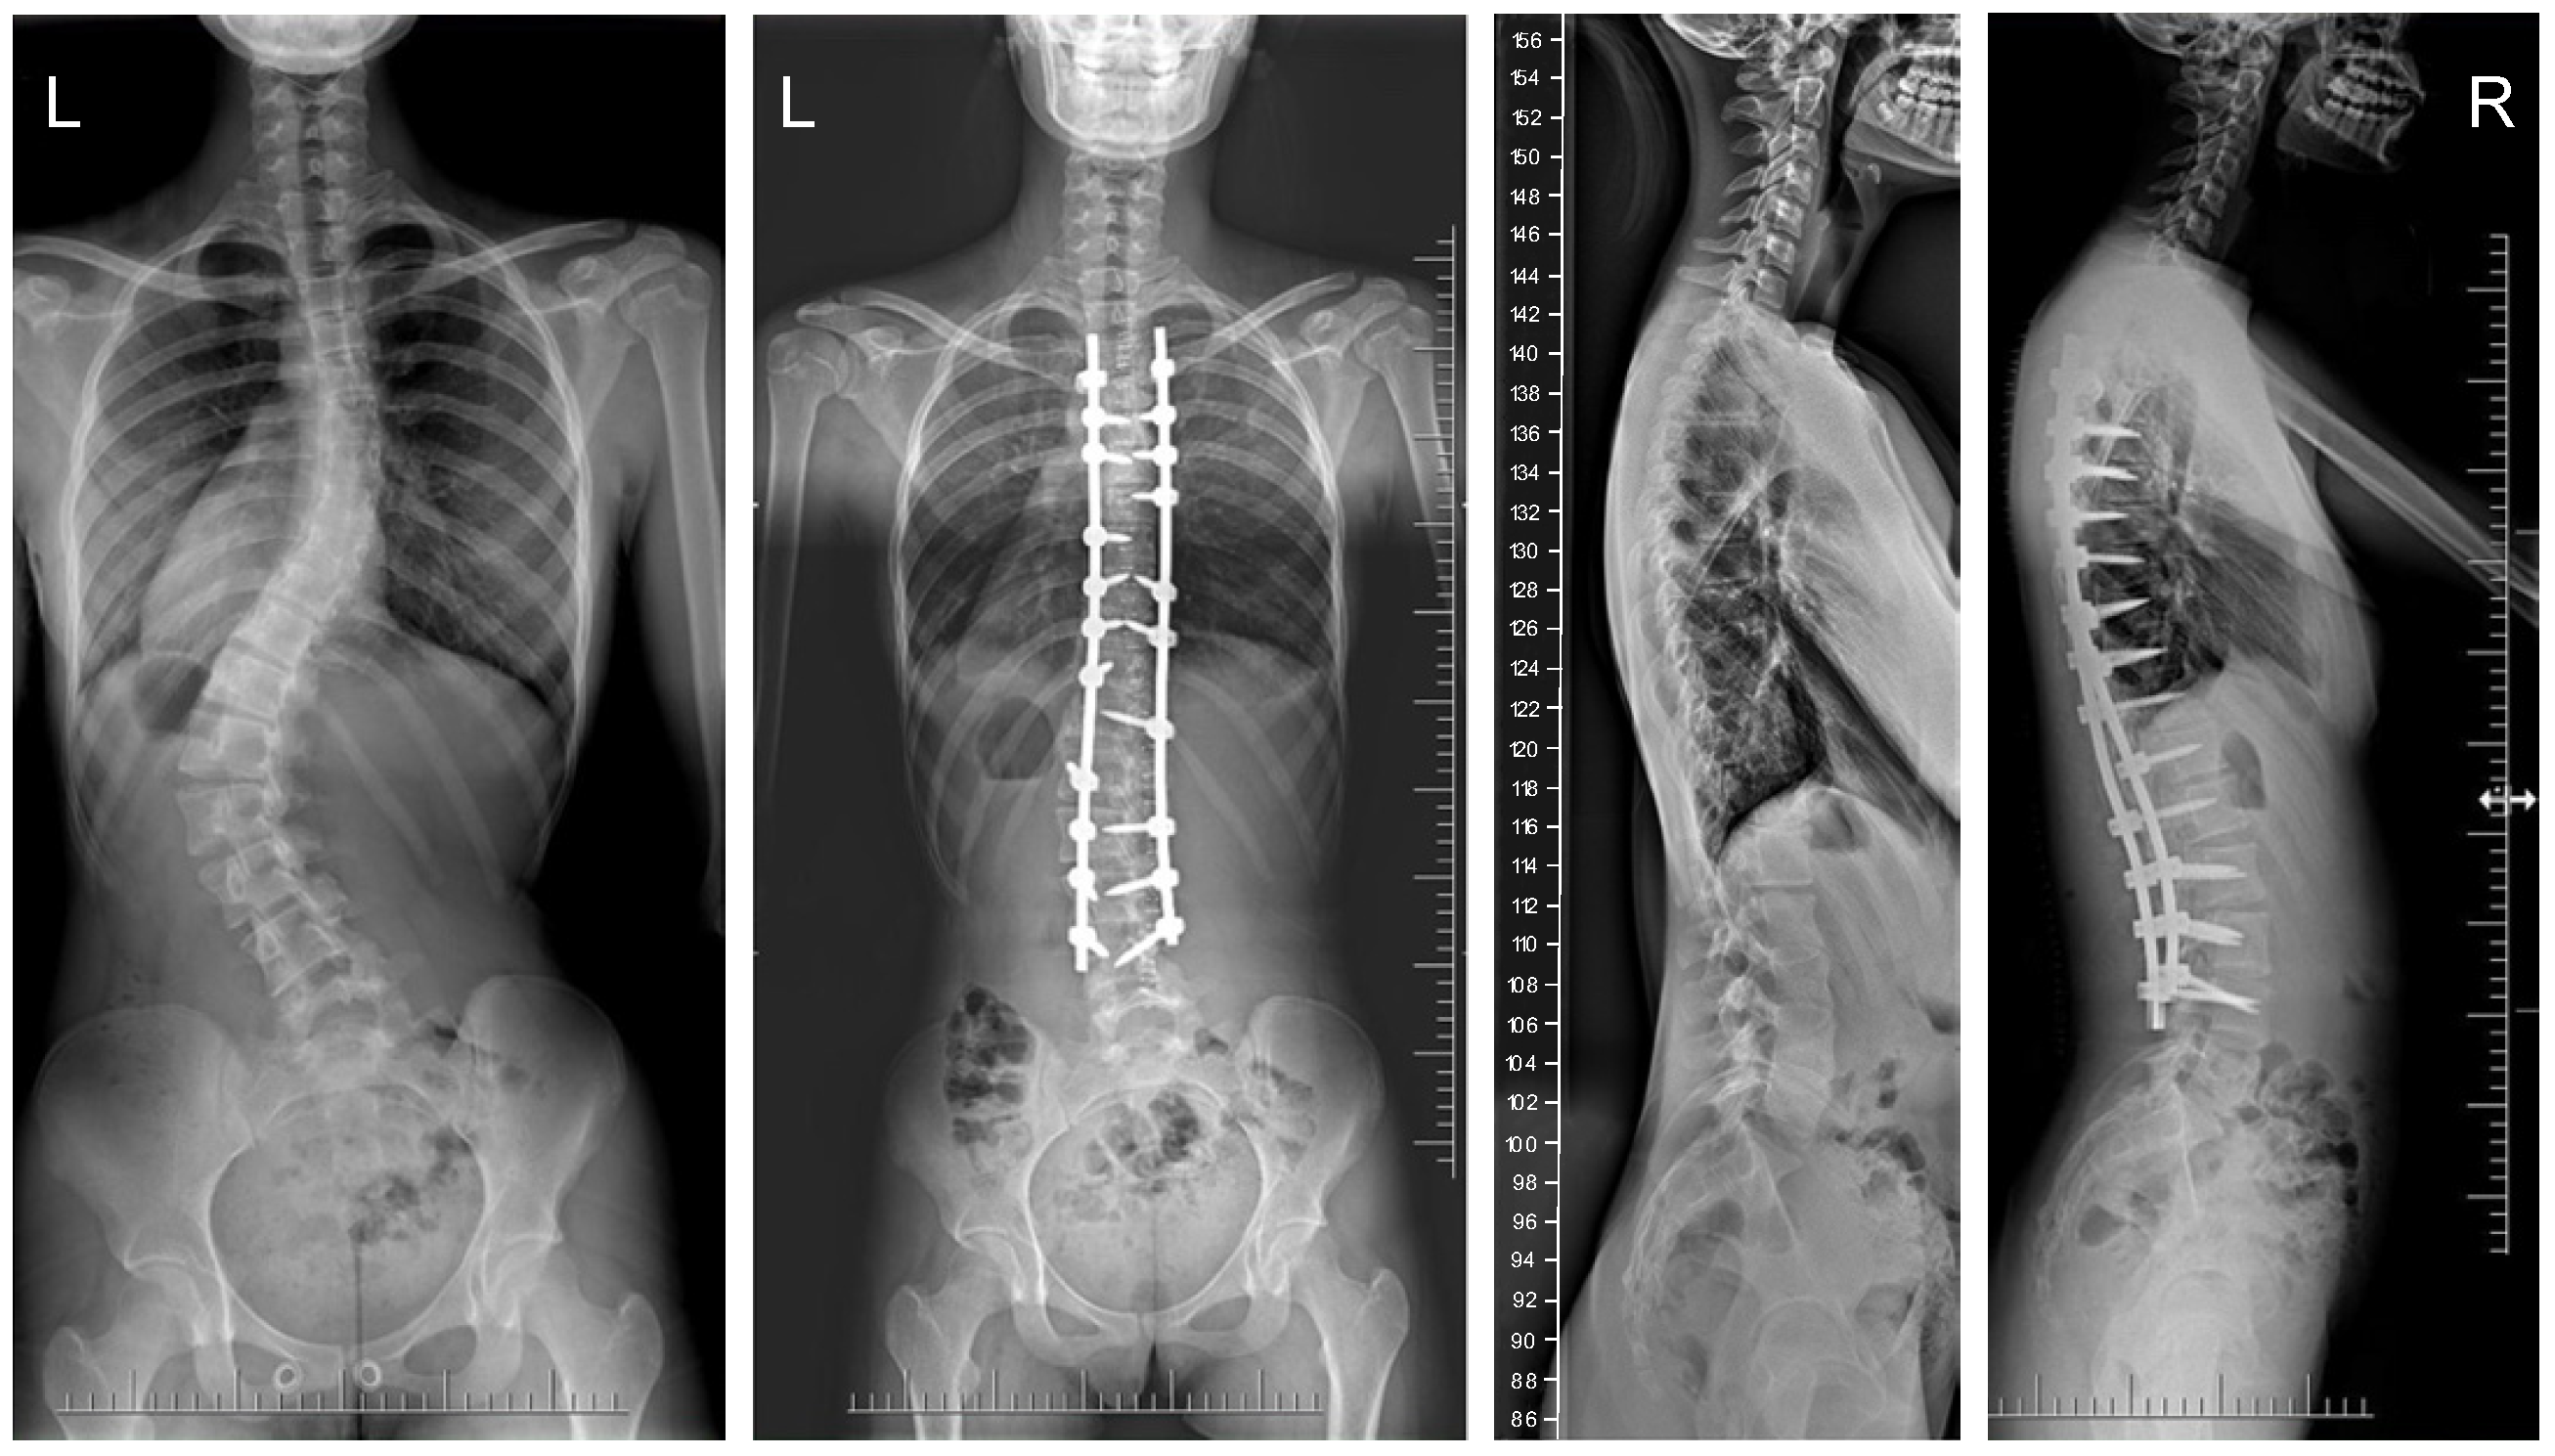

The mean (SD) operative times were recorded as 252 (62.4) minutes for the G1 patients and 344 (82.8) min for the patients in G2. The mean (SD) estimated blood loss levels were noted as 480 (288) mL for the patients in G1 and 632 (278) mL for G2. During statistical analysis, we found no statistically significant differences in either operative time or estimated blood loss between the study groups. The mean (SD) fusion levels were 10.2 (2.8) for G1, and 9.8 (3.2) for G2 (N.S.). The mean (SD) screw densities were noted as 75% (12) for the G1 group, and 75 (10) for the G2 group (N.S.). All analyzed data are presented in Table 1. Figure 1, Figure 2, Figure 3 and Figure 4 show X-rays of exemplary patients with idiopathic scoliosis after surgical treatment from G1 and G2.

Figure 3.

X-rays of a 15-year-old girl with AIS, treated with larger screw sizes of 6.0 and 6.5 mm and 2 cobalt–chromium rods of 6.0 mm (G2). X-rays show curve before surgery and correction after surgical treatment.

The correction of spinal deformities using modern systems based on the CD technique enriched with osteotomy techniques of the posterior column of the spine provides powerful opportunities for the correction and stabilization of curvatures [4,8,10,11,12,13]. Many details of implants have evolved and been improved, such as the implant profile, screw head stiffness, mobility in the sagittal axis, and its multi-axial nature, to obtain the best possible correction results [20,21,37,38]. The quality of the rod used is important in three-plane correction, i.e., the metal alloy (titanium, cobalt–chrome) and its diameter, which affects its ability to reproduce the sagittal and frontal balance of the spine [17,18,19,20,21]. It is known from other biomechanical studies that the larger the screw diameter, the better the stabilization and the lower the risk of screw removal and implant loosening [20,23,39,40,41]. For the surgical treatment of AIS, we received excellent outcomes using a system based on CD instrumentation in terms of three-dimensional correction of the spine (Figure 1, Figure 2, Figure 3 and Figure 4 show X-rays of exemplary patients with idiopathic scoliosis after surgical treatment from G1 and G2), the coronal and sagittal planes, derotation, and the clinical outcomes [11,12,13]. It should be emphasized that the correction possibilities of spinal deformation are influenced by other factors that we did not analyze, such as bone quality, so we focused on assessing the results of surgical treatment based on the sizes of the screws and rods used [39,40,41]. Also, the flexibility of the spine assessed on bending films is the main factor influencing the achievement of correction, as well as the loss of correction [42].